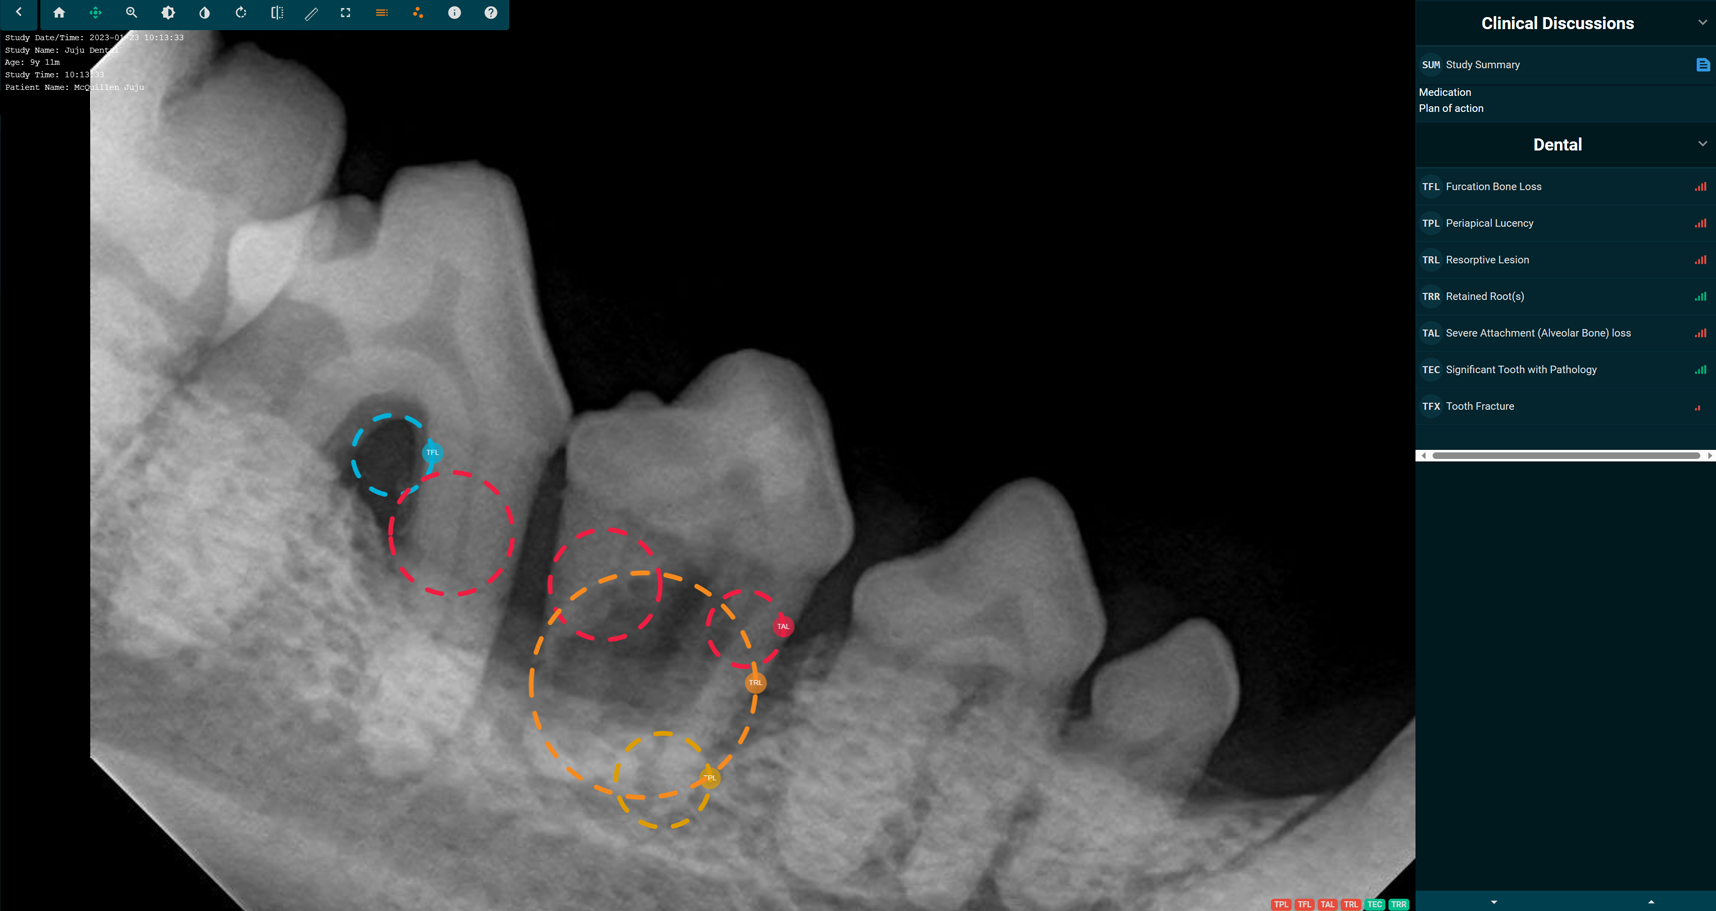

SignalSMILE's patenterade AI-teknologi för veterinärer använder maskininlärning för att i realtid bedöma röntgenbilder av sällskapsdjurs tänder för normalt och onormalt, för att hjälpa praktiker i diagnosprocessen.

Vår patenterade AI upptäcker det normala och onormala för de 7 vanligaste tandpatologierna och underlättar beslutsfattande vid vårdpunkt.

Medan du utför en grundlig rengöring arbetar SignalSMILE'S AI aktivt i bakgrunden för att ge resultat av de 7 vanligaste tandpatologierna.

Fatta informerade beslut

Att fatta beslut kring utdragningar bör inte tas lättvindigt. Med SignalSMILEs stöd kan du vara trygg i ditt beslutsfattande kring kirurgiska ingrepp för tänder med patologi.